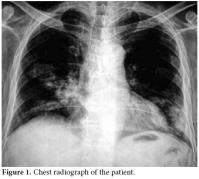

A 50-year-old male patient was admitted to our hospital with symptoms of fatigue, proximal muscle weakness, and bruising. Two years previously, he had manifested symptoms of arthralgia, arthritis, and edema. Because of these complaints, laboratory tests were performed. Nephrotic range proteinuria, a high creatinine level, bicytopenia along with antinuclear antibody (ANA) and Anti-deoxyribonucleic acid (anti-DNA) positivity were determined in these tests. Systemic lupus erythematosus was considered. Type ΙV lupus nephritis was also determined with a kidney biopsy. Endoxan 500 mg pulse and methylprednisolone 1000 mg pulse (3 days) were given to the patient parenterally. After these immunosuppressive treatments, the symptoms of the patient relieved, and corticosteroid treatment was continued as methylprednisolone 1 mg/kg/day at another hospital. The methylprednisolone dosage was not tapered accordingly, and after four months, suffering from fatigue, proximal myopathy, and weakness and the patient was admitted to our clinic. Upon physical examination, no other finding other than proximal muscle weakness was determined. Laboratory findings were white blood cell count: 12300/mm3, hemoglobin: 8.9 g/dl, hematocrit: 24%, MCV: 82 fL, lymphocyte: 200 mm3, platelet: 63000 mm3. Glucose: 79 g/dl, BUN: 109 mg/dl, creatinine: 2.7 mg/dl, uric acid: 8.4 mg/dl, Na: 135 mmol/L, K: 4.6 mmol/L, Cl: 105 mmol/L, Calcium: 8.2 mg/dl, P: 4.0 mg/dl, AST: 12U/L, ALT:39 U/L, LDH: 643 U/L, ALP: 70 U/L, and anti-dsDNA of 1:1280. Total bilirubin: 0.48 mg/dl, direct bilirubin: 0.06 mg/dl, Indirect bilirubin: 0.42 mg/dl, total protein: 5 g/dl, albumin: 2.39 g/dl, Fe: 73 mcg/dl, Iron binding capacity: 212 mcg/dl., PT: 11.1 sn, aPTT: 18.8 sn, INR: 0.90 were found. A chest radiograph taken on admission revealed multiple cavitary lesions (Figure 1). A chest computed tomography (CT) also showed multiple cavitary lesions at the sites of the right medial lobe, right inferior lobe superior segment, and left lingula inferior segment along with nodular lesions at the right inferior lobe superior segment (Figure 2). These lesions were found to be related with intensive and long-term steroid treatment. The cavitary lesions were considered as an opportunistic fungal infection, nocardiosis, or tuberculosis. A smear of sputum was negative for both Gram stain and acid fast bacilli, and cultures related to tuberculosis were found to be negative. A bronchoscopy and endobronchial lavage were performed to determine the etiology of these lesions. No endobronchial lesion was observed. Cultures for tuberculosis, nocardiosis, and fungal infections were taken from bronchoalveolar lavage, and also samples were taken for cytologic examination of lavage. In bronchoalveolar lavage fluid cytology, polymorphonuclear leukocytes was detected, and there were no atypical findings. The sputum specimen was also examined again, and cultures were sterile. The symptoms of the patient had increased progressively. The cavitary lesions had also increased. Because of this progression, high resolution computed tomography (HRCT) was performed. New cavitary lesions were determined at the left pulmonary site in HRCT. Nocardiosis was found positive in bronchoalveolar lavage fluid specimens. The patient was diagnosed as having pulmonary nocardiosis and given intravenous trimethoprim-sulfamethoxazole (320 mg/1600 mg/day), but the patient’s clinical findings worsened. Acute respiratory failure developed on the second day of treatment. Metabolic acidosis and respiratory alkalosis were added to the clinical findings. In arterial blood gas, PH: 7.31, PCO2: 24.8 mmHg, PO2: 35.6 mmHg, HCO3: 12.2 mmol, O2 saturation: 57.9% were found. Oxygen inhalation and anti-obstructive treatment were started. Sepsis and acute respiratory distress syndrome were considered possible , and the patient was sent to the intensive care unit. The patient died one day after being sent to the intensive care unit.

Pulmonary nocardiosis produces an impressive variety of roentgenographic findings, such as segmental infiltrates, lobar infiltrates, small and large cavities, necrotizing bronchopneumonia, necrotizing lobar pneumonia, lobar pneumonia with bulging fissures, small and large abscesses, single or multiple nodules, miliary patterns, masses with central cavitations, pleural effusion, and empyema.[5] Because the radiographic feature of nocardiosis is non-specific and pleomorphic with clinical findings ranging from malaise to respiratory failure, it is difficult to diagnose; therefore, the diagnosis of nocardiosis is often delayed. Multiple nodules and cavitation are more commonly described in acquired immune deficiency syndrome (AIDS) patients.[6,7] Multiple cavitary lesions are very rare in non-HIV patients. In our case, the patient was a man with a diagnosis of SLE, and he had undergone corticosteroid treatment for a long time. Although his test was negative for AIDS, multiple cavitary lesions were seen in his chest X-ray and HRCT. Since the patient was HIV-negative and immunosuppressive, all causes of multiple cavitary lung lesions were investigated. Tuberculosis, fungal infections, and malignancy were considered in the differential diagnosis. Multiple cavitary pulmonary nodules can be easily confused with a variety of other bacterial infections of the lung, including actinomycosis and tuberculosis as well as fungal infections and malignancies. In our patient, all of these causes were eliminated after all of the necessary tests were performed.

As shown in our case, pulmonary nocardiosis can be found in unexpected ways, especially in immunosuppressed patients. This patient showed multiple cavitary lesions on chest X-rays. The association of nocardiosis with SLE has only been rarely determined, and its association with acute respiratory distress syndrome has only been reported in one case.[14] In our case, acute respiratory failure was also found because of nocardiosis, and although treatment for infection was started, the patient died within a few days.

In conclusion, nocardiosis may become a severe infection, and it mainly affects profoundly immunocompromised patients. Differential diagnosis, especially with tuberculosis, often delays the time to a proper diagnosis, which worsens the outcome. New diagnostic tools, such as the polymerase chain reaction, could provide more rapid and reliable results. Nocardiosis should always be considered in the differential diagnosis of indolent pulmonary disease, particularly in the setting of cellular immunocompromise. Pulmonary nocardiosis is expected to be a more frequently-encountered disease due to the increasing use of immunosuppressive therapies. The disease should be considered in the differential diagnosis of multiple cavitary pulmonary nodules on chest radiography, even in HIV-negative immunocompromised patients receiving long-term corticosteroid treatment.